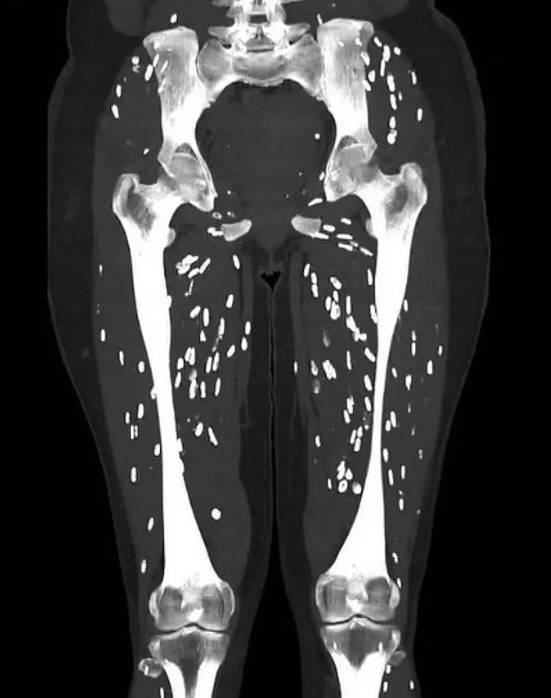

그러나 뇌 CT 검사에서 종양이 발견되면서 기생충 감염 가능성이 제기됐다. 이후 추가 검사를 통해 낭미충증 진단이 내려졌다.

낭미충증은 장, 근육, 피하지방뿐 아니라 뇌, 척수, 안구 등 여러 조직에서 발생할 수 있다. 뇌에 침투하면 두통, 발열, 구토, 식욕 부진 등 일반 증상과 함께 발작, 뇌염, 뇌압 증가, 수두증 등 심각한 신경학적 합병증을 유발할 수 있다.

진단은 대변 검사, 조직 엑스레이, CT, MRI, 뇌척수액 검사, 조직 검사 등 다양한 방법으로 이뤄진다. 치료는 경증일 경우 알벤다졸, 프라지콴텔 등 구충제 투여가 기본이며, 필요 시 물혹 제거를 위한 수술도 병행한다.